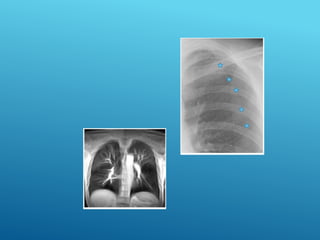

Contusión pulmonar

Diagnóstico

Antecedente traumático, Radiografía tórax revela:

Opacificación localizadas a un segmento o a un lóbulo.

Fracturas costales o no., La relación Pa 02/Fi 02 es menor de

CONTUSIÓN

PULMONAR